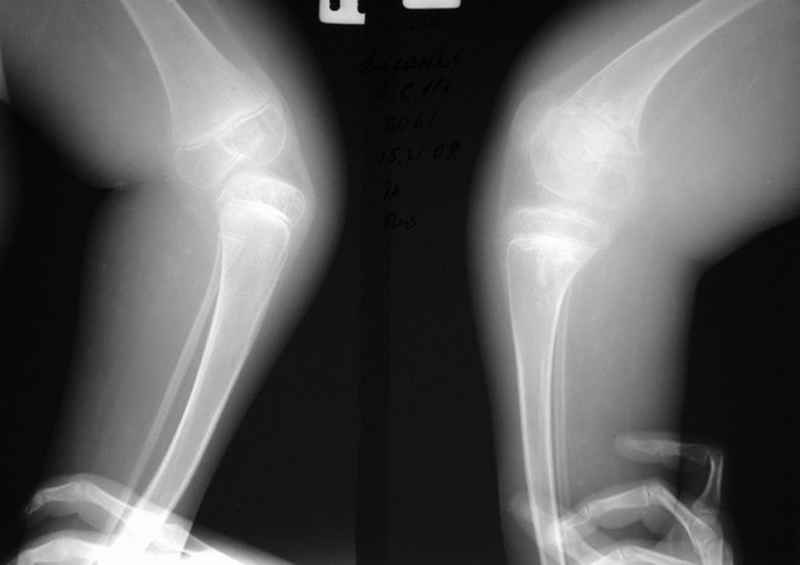

Диагноз. Артрогрипоз. Врожденные двусторонние вывихи бедер. Рецидивирующая двусторонняя врожденная косолапость тяжелой степени (состояние после оперативной коррекции в 2004 году с обеих сторон). Мягкотканные разгибательные контрактуры коленных суставов. Атрофия мышц голеней. Значительное нарушение функции нижних конечностей.

Место болезни. Передвижение ребенка резко нарушено, нижние конечности имеют атрофированный вид, мышцы голени дряблые, истончены. Форма всех суставов нижних конечностей деформирована. Коленные и тазобедренные суставы в положении разгибания. Сгибание и разведение тазобедренных суставов резко ограничено, имеет место их выраженная приводящая контрактура. Сгибание коленных суставов возможно до 90 , но при этом отмечаются болевые ощущения. Со слов мальчика: он боится сгибать коленные суставы из-за имевших место болезненных подвывихов голеней кнаружи. Клинически определяется невыраженная нестабильность коленных суставов - патологическая подвижность кнаружи (больше слева). Правая нижняя конечность короче левой на 8 см. Скарповские треугольники расширены. Ягодичные области симметричные. Ромб Михаэлиса симметричен, Явной деформации позвоночника не выявлено (в положении лежа и сидя). Оба коленных сустава деформированы, незначительно вальгированы (до 10 ), сгибание их резко ограничено. Стопы и голеностопные суставы деформированы, имеются п/о рубцы цвета кожи по задней и внутренней поверхностям голеностопных суставов и стоп. Сохраняется выраженное эквиноварусное положение обеих стоп, выведение их в правильное положение не возможно: приведение передних отделов стоп до 45 , супинация 45-50 , эквинус более 90 , движения качательные.